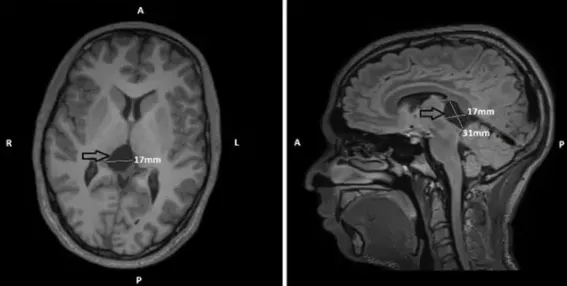

儿童被误判为“嗜睡”,临床诊断提示其大脑处于“功能抑制”状态,需紧急手术干预!此种无力感已持续困扰该家庭超过十年,其严重程度远非“懒惰”或“睡眠不足”等简单归因所能解释。...